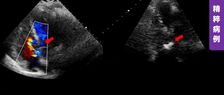

近期,沈阳医学院附属第二医院马晶茹教授团队成功应用MemoLefort左心耳封堵器,为一名71岁高龄房颤患者完成完成“射频消融+左心耳封堵”一站式手术。由于该病例心耳位置较低,术者选择房间隔低位穿刺,满足更好轴向,避免心耳上缘压迫,后通过DSA与ICE精准指引,利用MemoLefort封堵器的贴壁成角倒刺设计实现稳固锚定与严密封堵。